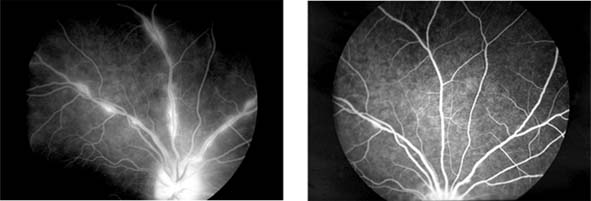

Figure 15-25

Figure 15-25: Sarcoidosis. Focal periphlebitis and disk leakage may respond dramatically to systemic corticosteroids. Left: Before treatment. Right: After 6 weeks of treatment with prednisolone, 30 mg daily.